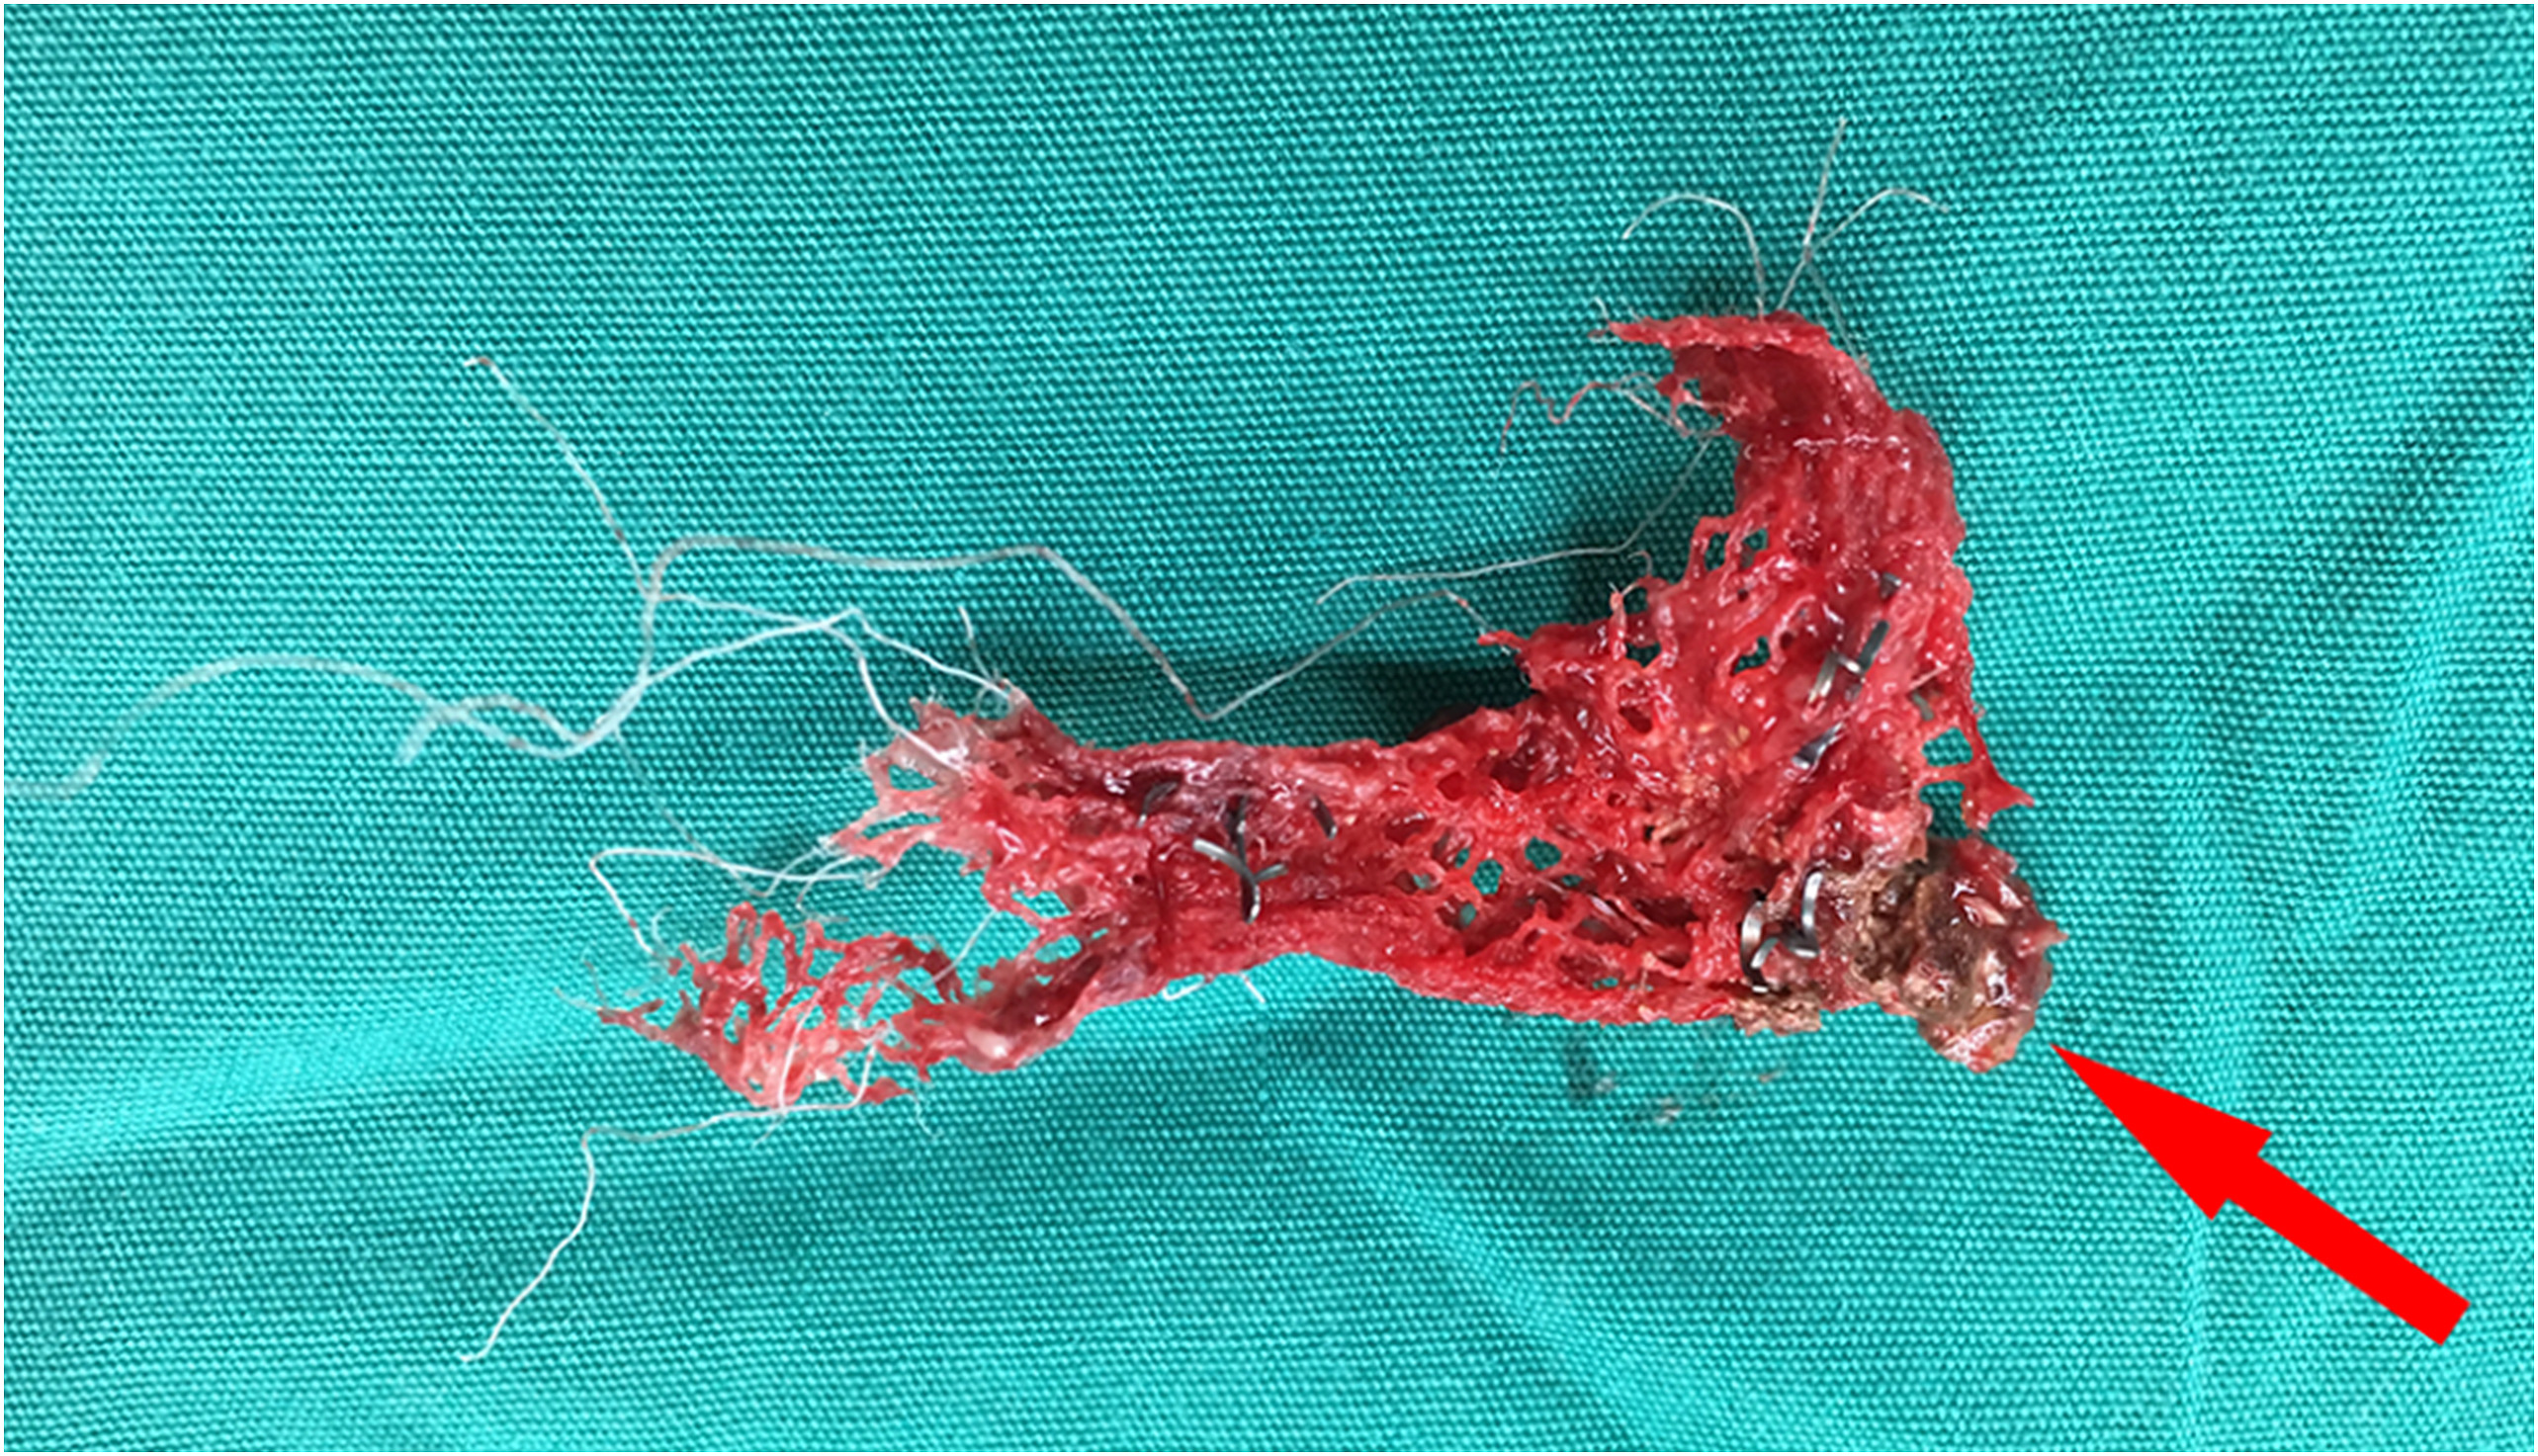

患者经抗生素治疗并排除恶性肿瘤后,行膀胱部分切除术和膀胱结石取出术(图3)。该院医生在手术中,只取出了部分侵蚀的网片(不是整块)和结石。最后,医生将膀胱缺损闭合,插入耻骨上引流管

和导尿管。患者恢复顺利,于术后第8天出院。随访期间,患者情况良好,无长期并发症。

图3 与网片融合在一起的膀胱结石(红色箭头)